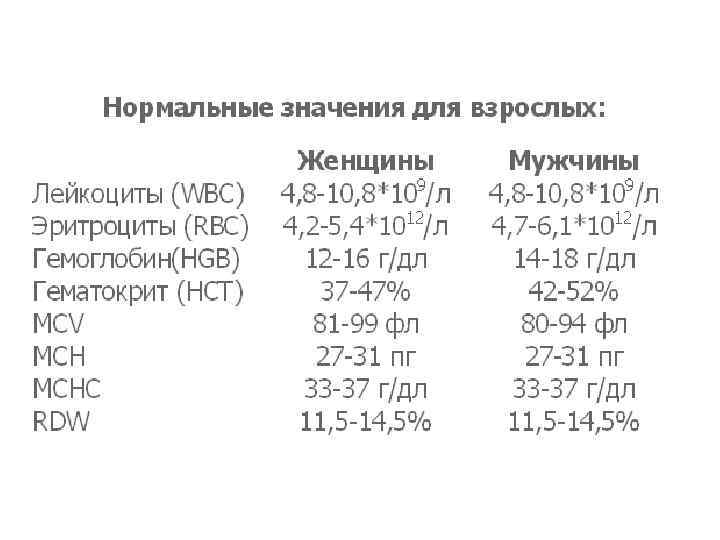

• Материал для исследования: венозная или капилярная кровь. Кровь берется с ЭДТА

• Материал для исследования: венозная или капилярная кровь. Кровь берется с ЭДТА

• Определение количества лейкоцитов, эритроцитов, показателей гематокрита и концентрации гемоглобина – этот комплекс чаще всего проводимых в лаборатории анализов, известен под названием гемограммы.

• Определение количества лейкоцитов, эритроцитов, показателей гематокрита и концентрации гемоглобина – этот комплекс чаще всего проводимых в лаборатории анализов, известен под названием гемограммы.

Морфологию эритроцитов характеризуют: • средний объем эритроцита (МСV – mean corpuscular volume), • среднее содержание гемоглобина (МСН - mean corpuscular hemoglobin) • средняя концентрация гемоглобина (МСНС - mean corpuscular hemoglobin concentration).

Морфологию эритроцитов характеризуют: • средний объем эритроцита (МСV – mean corpuscular volume), • среднее содержание гемоглобина (МСН - mean corpuscular hemoglobin) • средняя концентрация гемоглобина (МСНС - mean corpuscular hemoglobin concentration).

Морфологию эритроцитов характеризуют: • Автоматические методы измерения сделали возможным ввести ряд дополнительных параметров, среди которых особого внимания заслуживает показатель анизоцитоза эритроцитов – RDW(red cell distribution width).

Морфологию эритроцитов характеризуют: • Автоматические методы измерения сделали возможным ввести ряд дополнительных параметров, среди которых особого внимания заслуживает показатель анизоцитоза эритроцитов – RDW(red cell distribution width).